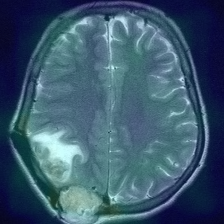

Figure 1: Heatmap Comparison of Unhealthy Images. Different columns show unhealthy MRI images of different positions, sizes, and textures. The first row is the raw image. The second row is the heatmap predicted with PatchCore. The third raw is the heatmap predicted with the proposed method.